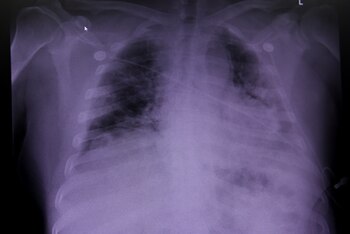

En los peores días de la pandemia de COVID-19 en Asia, en Europa y en los Estados Unidos los médicos se encontraron con un fenómeno tan incomprensible como idéntico: algunos pacientes llegaban a las salas de emergencia por sus propios medios y no parecían sufrir trastornos respiratorios de gravedad, pero sus niveles de oxígeno en la sangre indicaban que estaban cerca de necesitar un respirador.

¿Sufrían del síndrome de dificultad respiratoria aguda (SDRA), un cuadro raro pero crítico, o el coronavirus presentaba un enigma totalmente original? La hipoxemia —la falta de oxígeno en la sangre— era severa pero los pulmones funcionaba bien: no estaban rígidos, como suele suceder en el SDRA. Las discusiones y los estudios comenzaron en ese mismo momento, pero solo ahora, y casi por casualidad, se logró comprender qué sucede en realidad.